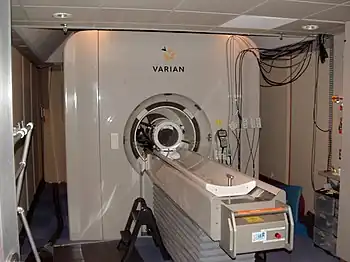

A 3 tesla MRI scanner fMRI scanner

fMRI scanner Rotating anode X-ray tube